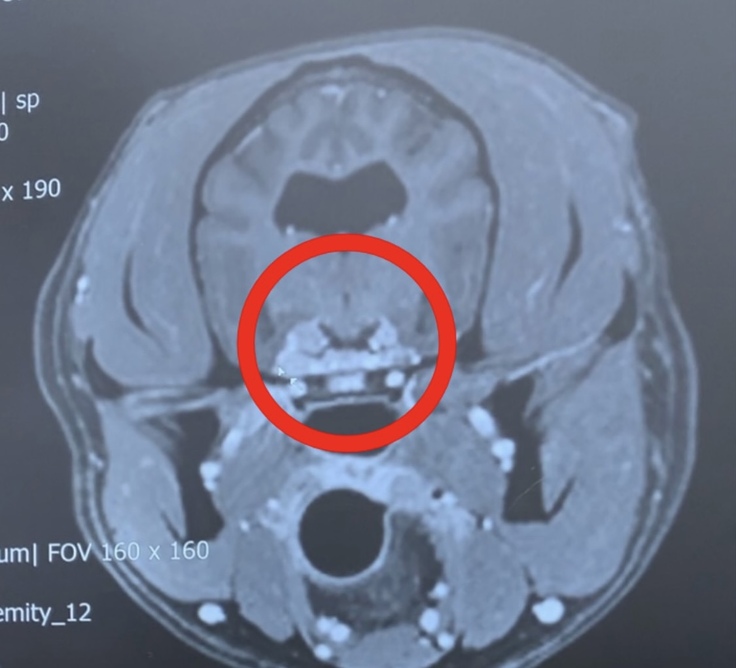

↑こちらの写真は、MRI画像です。

〇印をつけてある所がシャンティを苦しめている脳腫瘍です。

三叉神経・動眼神経です。

向かって右側よりも左側の方が大きい。

そして、とても小さいけど右側も腫瘍があると診断を受けています。